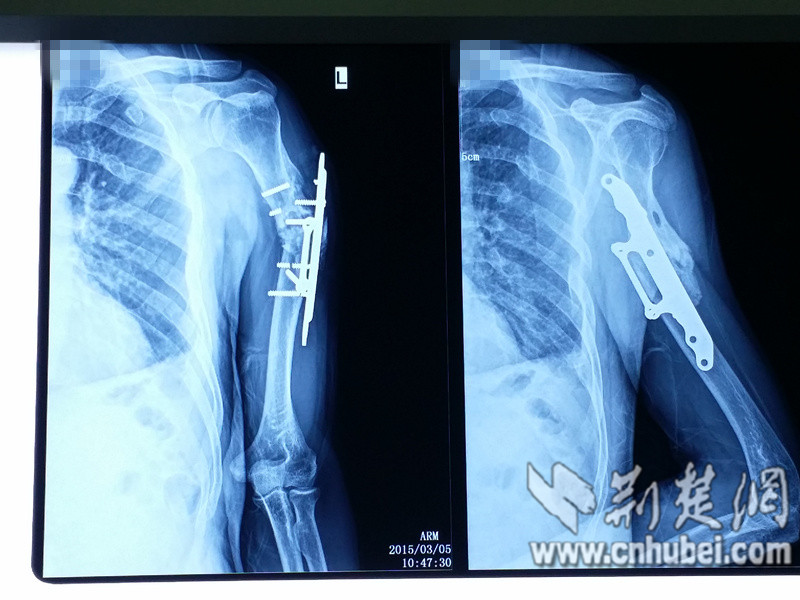

荆楚网消息(通讯员 杨敬慈 王皓)现年53岁的赵先生于1994年因车祸撞断左臂,送医上钢板后,他并未过分在意,为了生计,一个月后便又投入体力工作,提拿重物。约半年左右,他左臂伤口处皮肤出现一个小凸起,一摸竟然是硬的,好像是上的钢板的一端,不过上臂还是能活动的,他便不管不顾拖着不太灵活的手继续勤勉地工作,也没有及时到医院就诊。

时隐时痛一直持续二十年后,今年除夕前夜,在洗澡换衣服时,他发现曾经的伤口处有一个圆圆的银色东西,再仔细一瞧,呀!竟是钢板的一端,已彻底戳破皮肤外露,皮肉开始明显感到被磨得生疼,手臂也很难抬起。他这才来到武汉市第一医院骨关节外科就诊,后经手术处理治愈。

武汉市第一医院骨关节外科副主任医师徐礼森介绍,根据目前病情分析,可推断当初赵先生骨折上钢板后,其左臂骨骼并没有愈合,又经提拿重物等体力运动加剧损伤,被撞断的骨骼断端两头经磨损的碎骨已经成为死骨,并形成一个“假关节”。骨折长期不愈合并形成死骨后,即使清理死骨再取髂骨植入此处,后期愈合恢复也较难。

如今,赵先生的钢板上端已经完全断裂,剩余钢板钉嵌入上臂骨骼,且因“年久失修”,时隔20年之久,其使用的钢板钉型号都已于市面上少见。所以,“钢铁侠”患者应多关注自身钢铁之躯,若出现钢板处疼痛应及时就医,以避免“一朝钢露骨”。